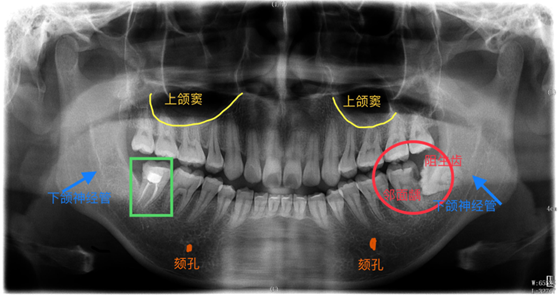

曲面断层全景片可发挥以下作用:

①判断整体牙齿情况、龋坏、残根或缺失情况;

②判断整体牙周情况、牙槽骨健康及吸收情况;

③判断阻生牙与周围牙体及结构,如下颌神经管的位置关系;

④判断颞下颌关节的对称度及形态情况;

⑤对上下颌骨、上颌窦、窦底轮廓等解剖的健康情况判断;

⑥对患者颌面部肿瘤、囊肿、畸形等的筛查和鉴别;

⑦对外伤患者上下颌骨、颧骨骨折形态、牙根情况的判断;

⑧对儿童乳恒牙牙胚、牙列等的发育情况判断;

举个例子,上图中患者由于右下后牙区反复溢脓就诊,口内显示右下第一磨牙颌面龋坏,拍片显示右下后牙区下颌骨可见一右下智齿的含牙囊肿。这种情况如果不拍片,仅根据临床检查,直接做右下第一恒磨牙的根管治疗,就造成漏诊和误诊。